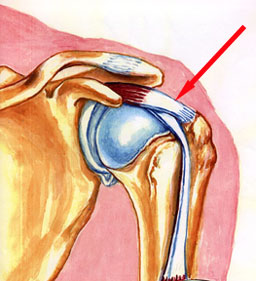

Normal Rotator Cuff Model